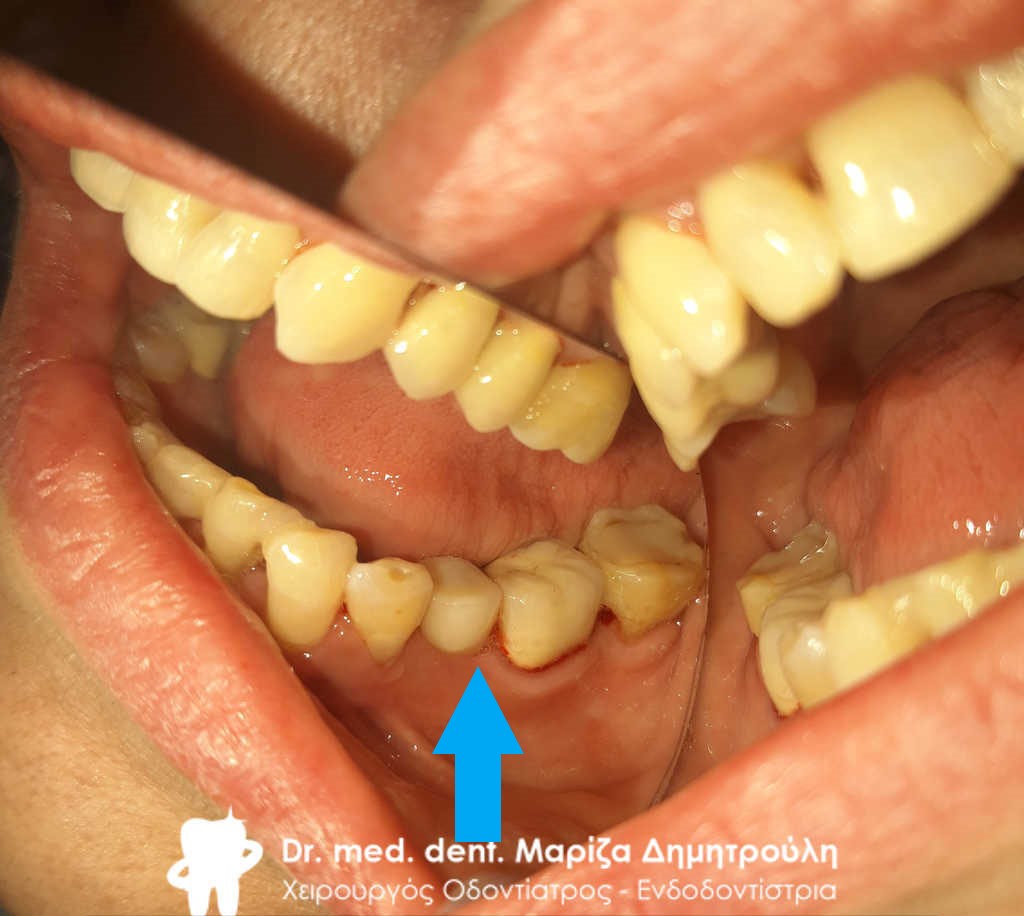

Περιστατικό – Ολοκεραμική θήκη ζιρκονίου στον αριστερο γομφίο της κάτω γνάθου

Ο πρώτος γόμφιος στην αριστερή πλευρά της κάτω γνάθου είχε απονευρωθεί στο παρελθόν. Ο ασθενής δεν θέλησε να καλύψει το δόντι με θήκη, ώστε να είναι πλήρως προστατευμένο με αποτέλεσμα το δόντι να σπάσει (όπως φαίνεται στην αρχική εικόνα). Η λύση θεραπείας ήταν η κατασκευή στεφάνης δοντιού, αφού προηγουμένως το δόντι τροχίστηκε καταλλήλως και ο οδοντοτεχνίτης κατασκεύασε την ολοκεραμική θήκη ζιρκονίου.

Το δόντι είναι πλέον πλήρως προστατευμένο και μπορεί να αντέξει στο πέρασμα των χρόνων.

ΠΡΙΝ

ΜΕΤΑ